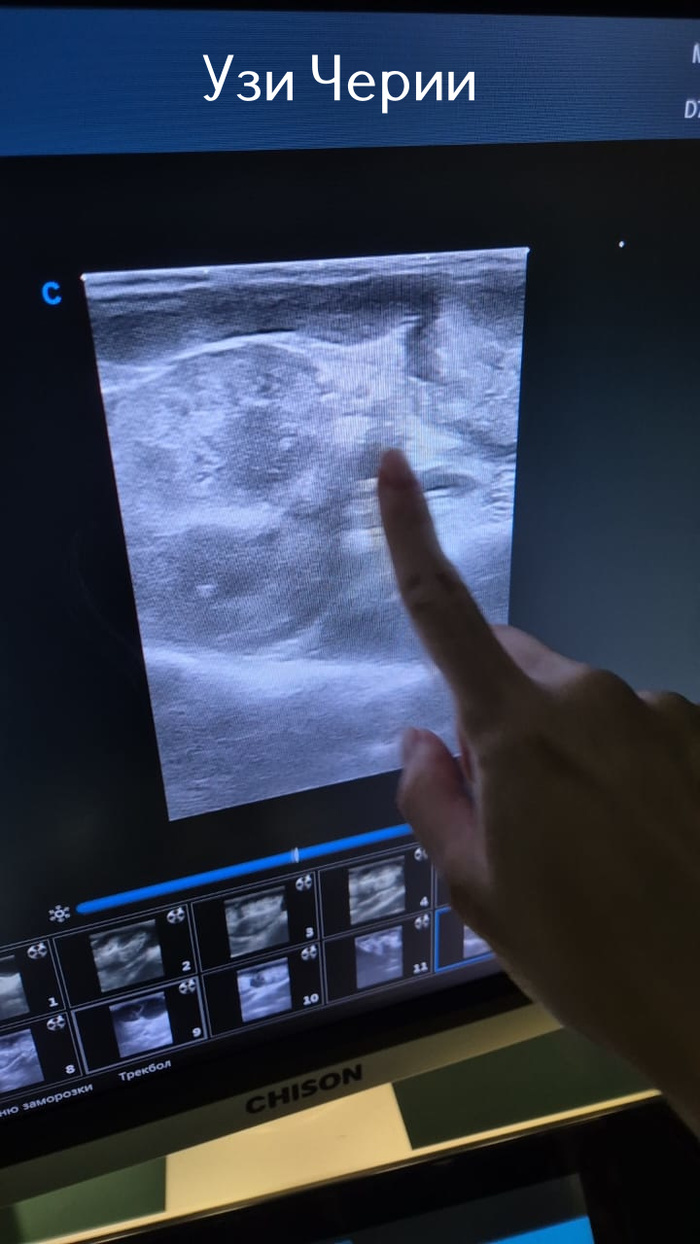

Вчера вечером отказалась от еды Черри. Сегодня утром ей стало хуже и уже в восемь утра её отправили в клинику. Там, в числе прочего, ей сделали УЗИ и выявили большое количество кист на почках. И какие-то спайки между почками. Решили сделать операцию и во время неё выяснилось что всё бесполезно и ей оставалось лишь несколько дней мучений... Черри теперь на радуге... Опять уже подзабытая боль в душе и в сердце навалилась. Если честно даже писать больше ничего не хочется сегодня. Этот текст уже час пытаюсь набрать...

Узи Черри